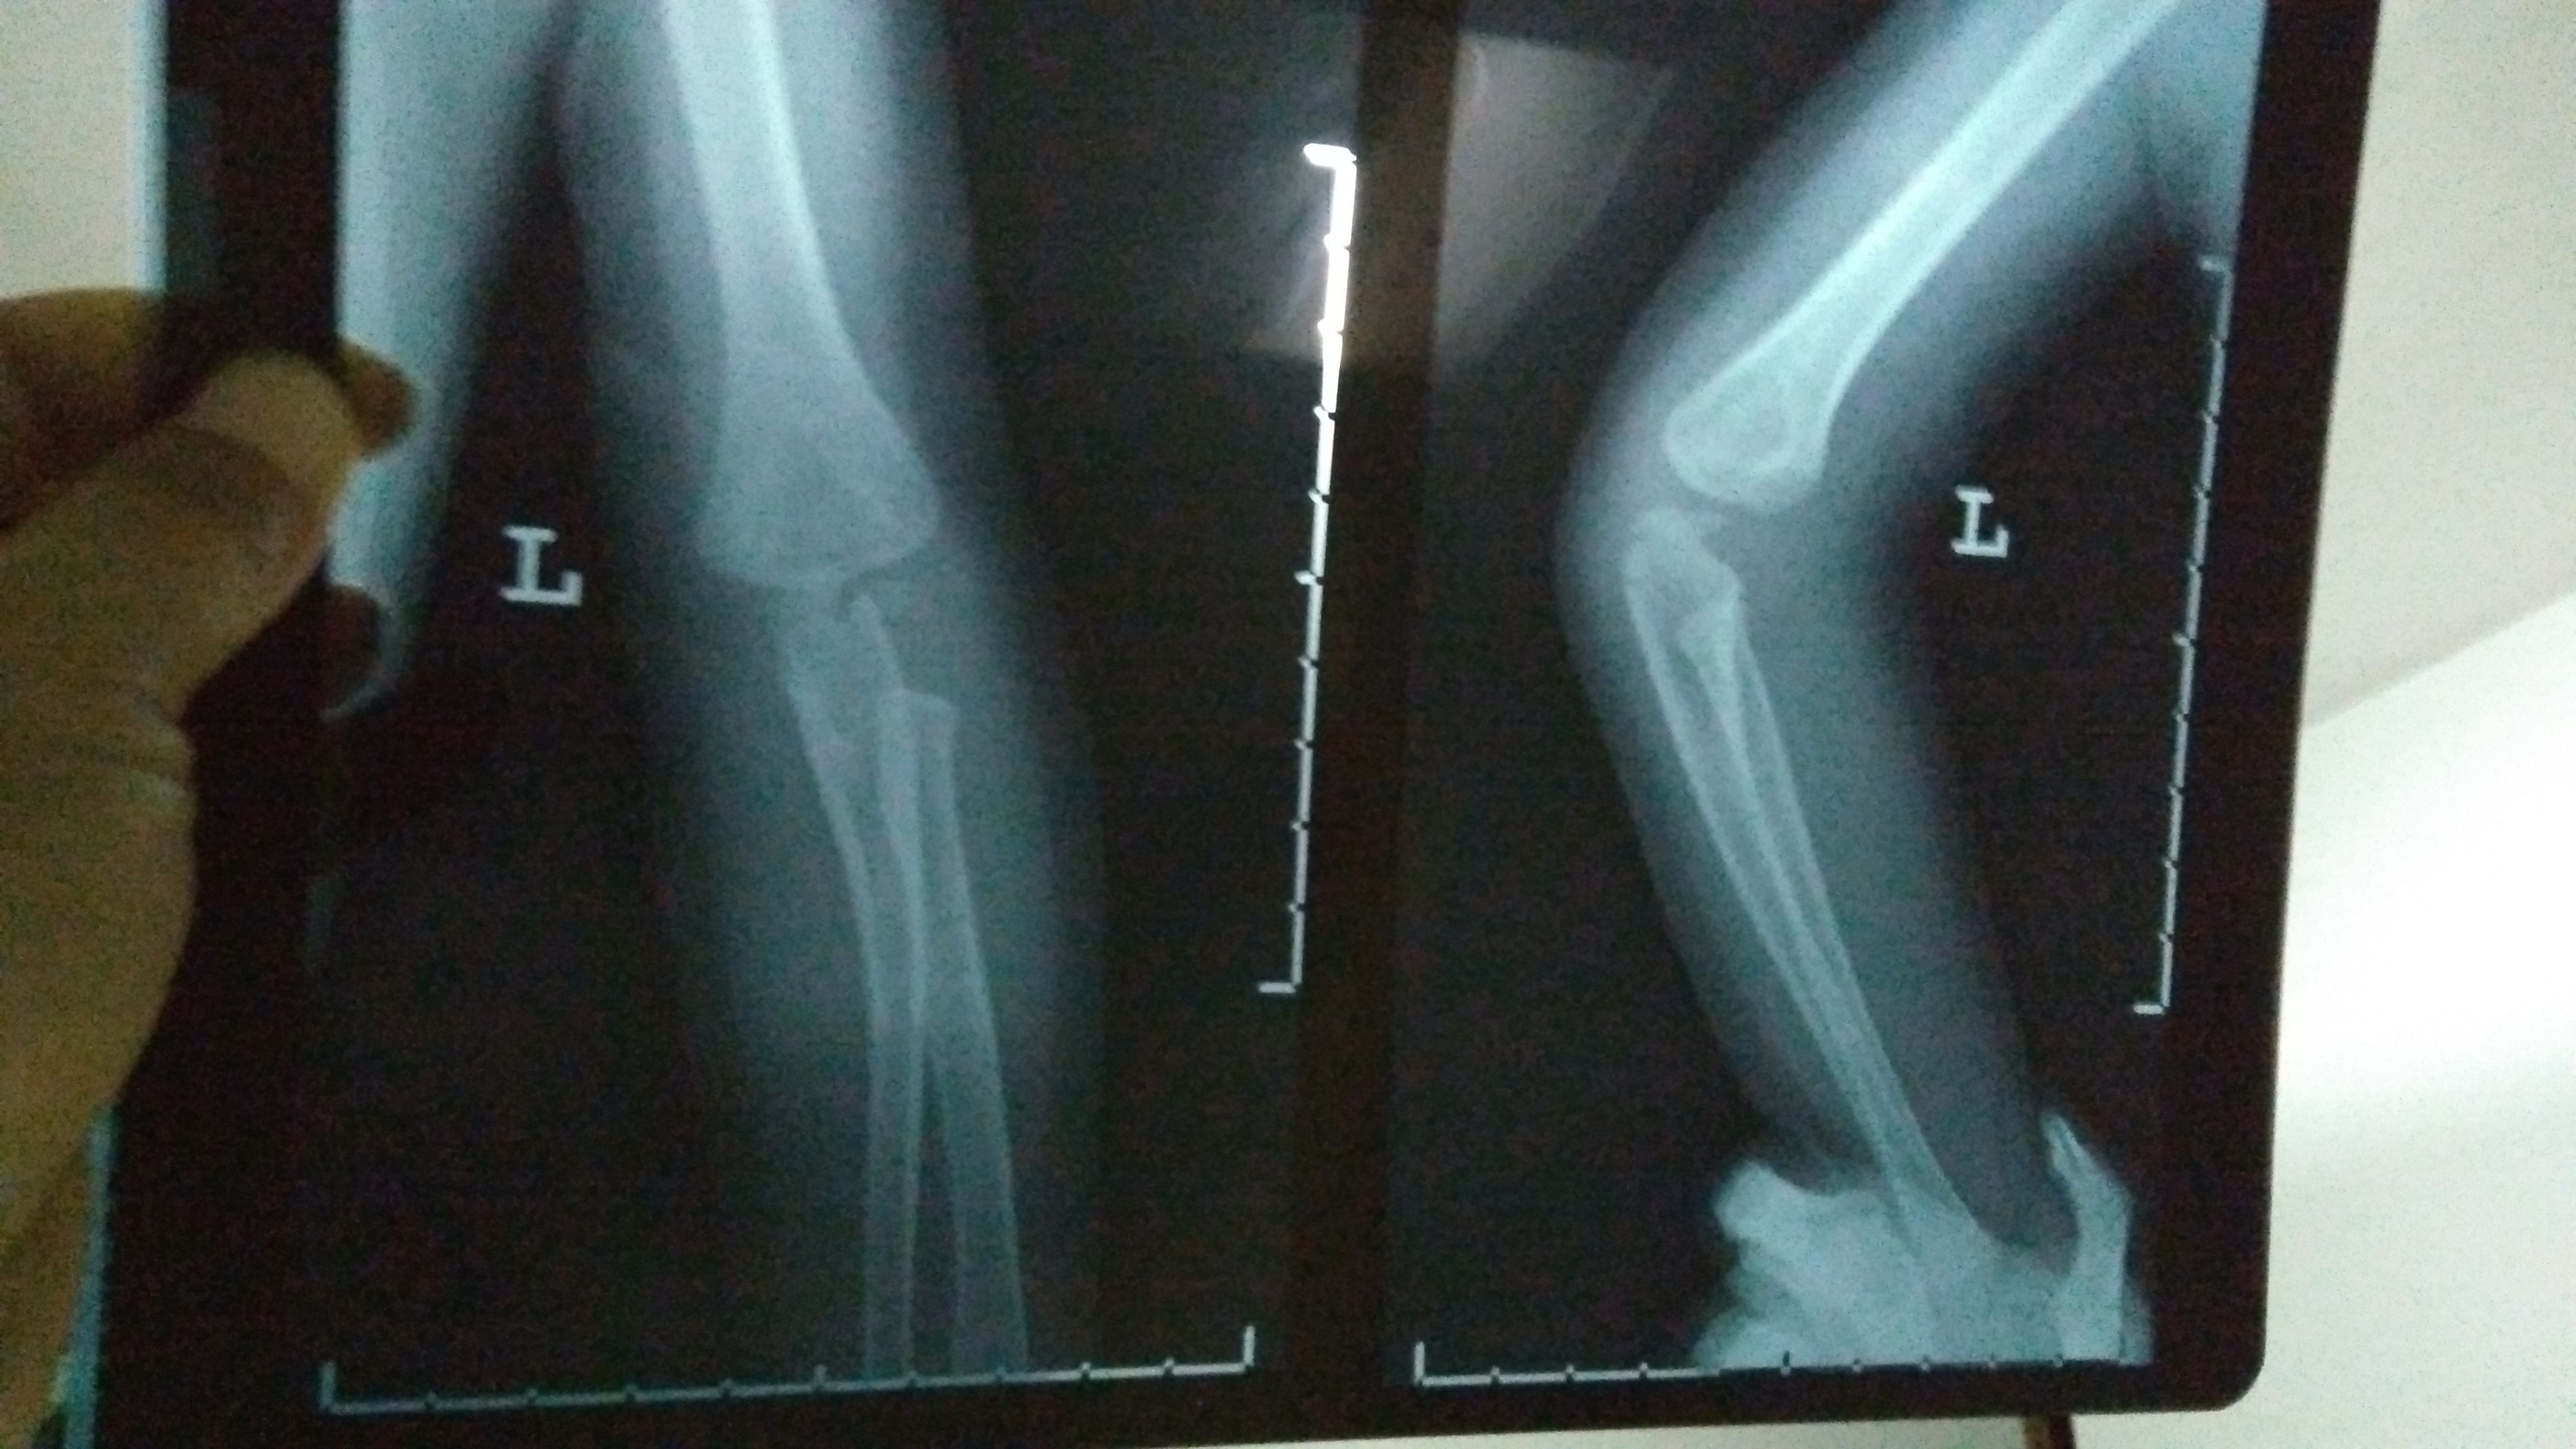

2岁宝宝骨折,急急急! 宝宝今晚玩耍奔跑时,摔倒姿势有异(速度很快不小心扑倒了,整个左手臂压在他自己身下,当时就骨折了)。 宝宝一直出冷汗表情痛苦哭,左手不动弹,我们赶紧去医院。以下是X光片(左手)和报告,打了石膏,医生让4-7天内去复查。 另外医生说小儿骨折这个部位骨垢骨折的情况比较少见,需要我明天带着片子报告去给他们主任看一下,看是否会影响手臂的功能性。如果有功能性影响,会影响孩子发育,还得纠正,做手术。 我知道医生总是会预先把最坏的结果告知患者,可是伤在儿身,痛在娘心。我担心害怕要做手术,加上回家后老公一直在说医生当时石膏没打好,让我带宝宝明天去重新打过石膏…说医生不太靠谱。确实,那个医生打石膏的时候还在接电话,一直不停跟他家人打电话接电话。 恳求有懂小儿骨折的医生帮帮我,看看我宝宝这个情况到底怎样?会影响他发育吗?可能要做手术纠正吗?跪求了!万分感谢!

这个部位骨折是非常清楚的,先打石膏固定一下(不可重复打石膏),看看恢复情况,如果效果不好一周之内要手术治疗!